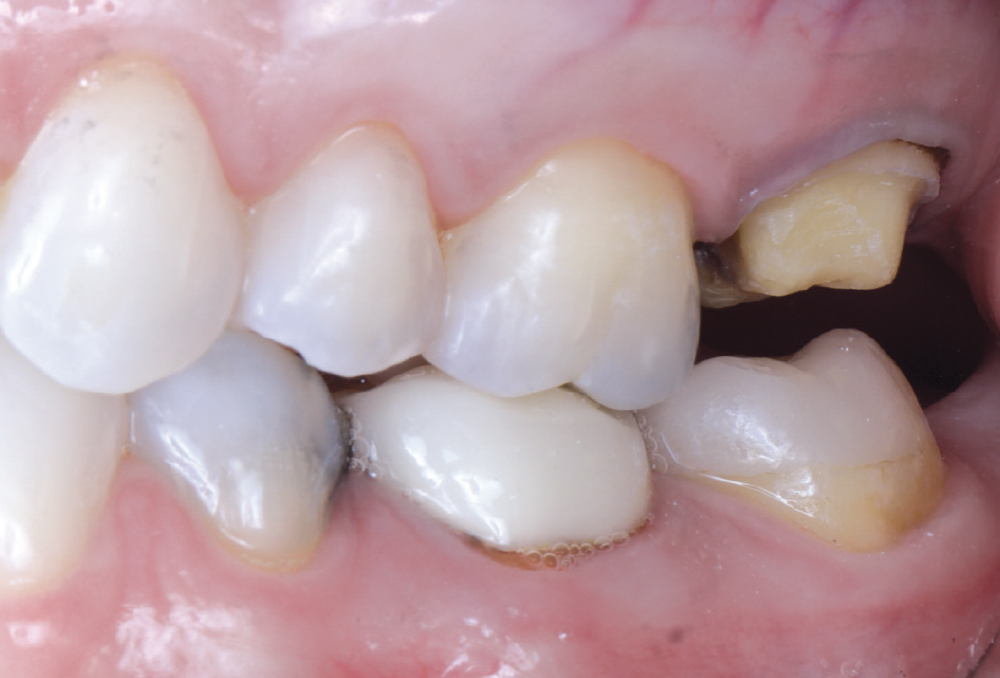

Even though she is a dental hygienist, Nikole decided to wait it out when she was told her crown on tooth #15 had an open margin. But over time, she noticed the area started to shred her floss. That’s when she decided it was time for the crown to be replaced.

I enjoy using the glidewell.io system because I can provide a high-quality, same-day restoration. I’m in control of the contacts, shape, color and fit. The crown fits with minimal adjustments needed.

This was Nikole’s first experience with same-day dentistry, and she summed it up best: “I’m a fan! The new crown fit perfectly, with no return visit, no second round of anesthesia and barely any adjustments. The contacts are spot on, and flossing feels smooth.”